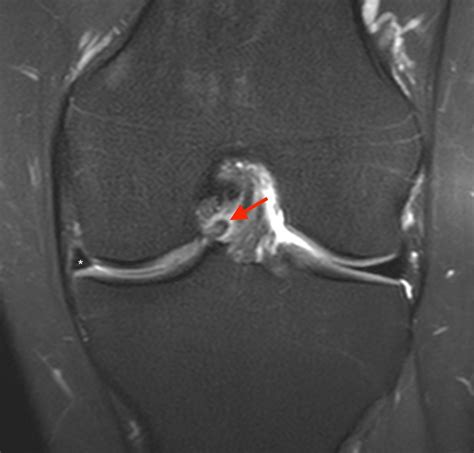

A Bucket Handle Injury is a specific type of meniscal tear that occurs in the knee. The meniscus is a C-shaped piece of cartilage that acts as a shock absorber between the thighbone (femur) and the shinbone (tibia). When a tear occurs in a way that the inner portion of the meniscus flips up into the joint, it is called a bucket handle tear because it resembles the handle of a bucket.

• MRI (Magnetic Resonance Imaging): To provide detailed images of the soft tissues, including the meniscus, to confirm the diagnosis.